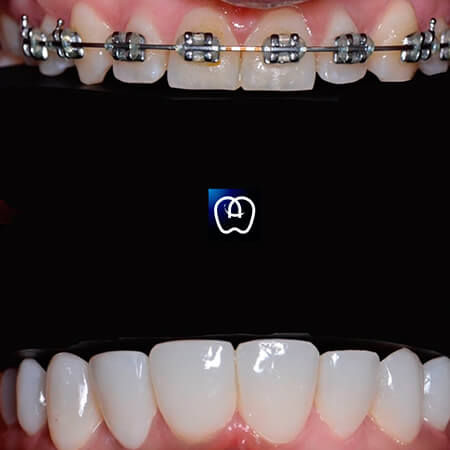

Orthodontics with metal brackets performed by the dentist Emanuel Rodríguez